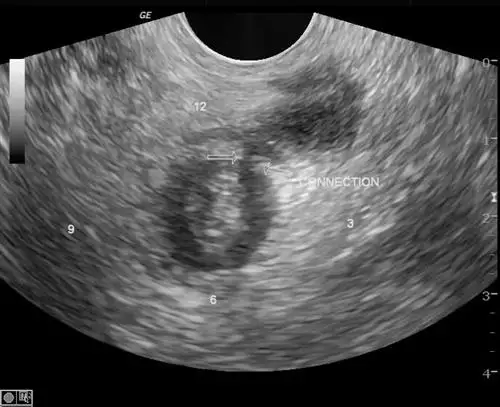

微创手术技术也是肛周脓肿治疗的重要方向。通过超声引导下的微创手术,可以精准定位脓肿位置,进行微创引流和清除病灶。微创技术的应用,有助于减轻患者的痛苦,加速术后康复。